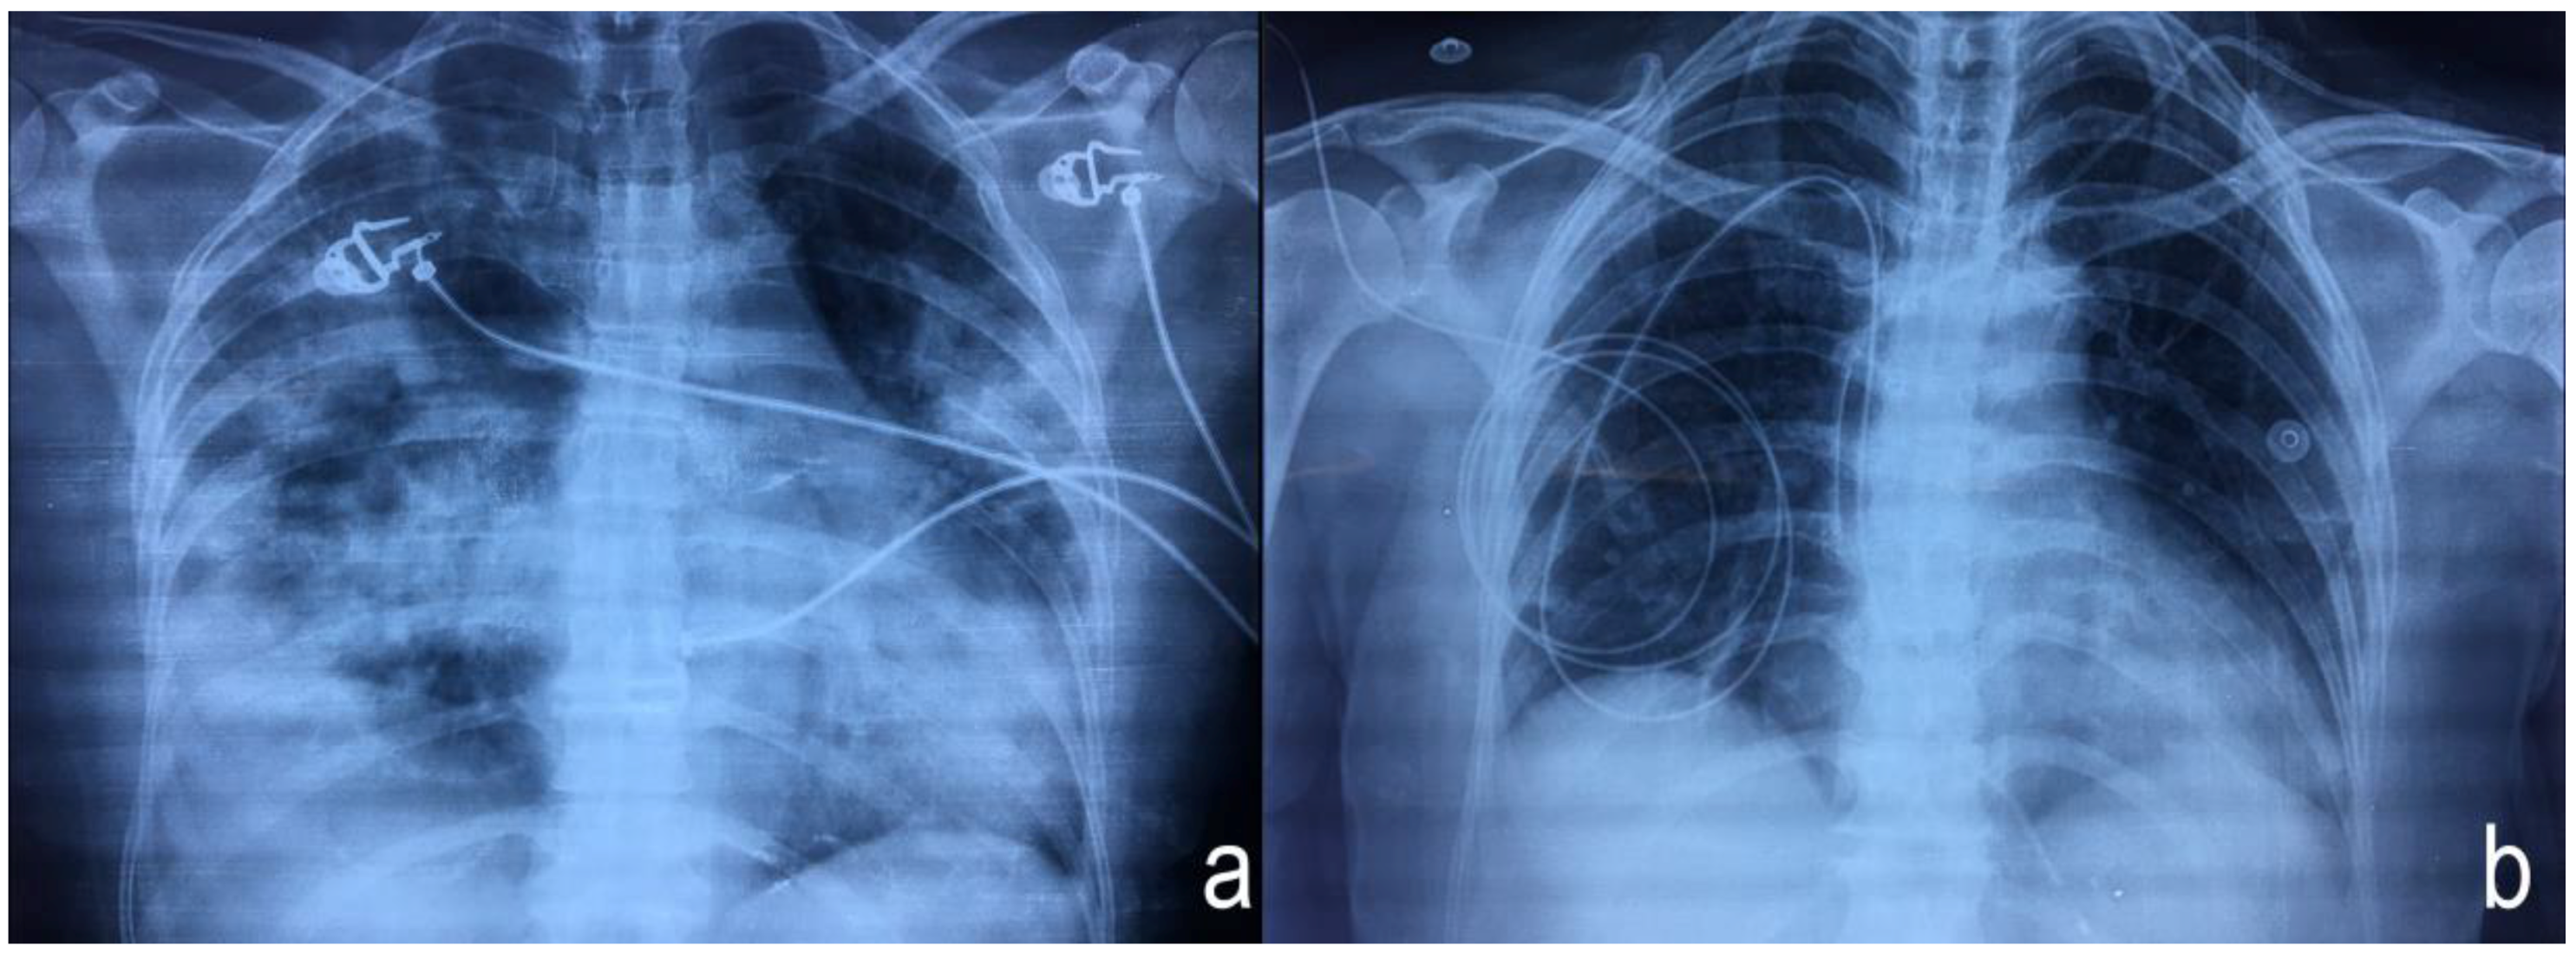

3. Case Presentation